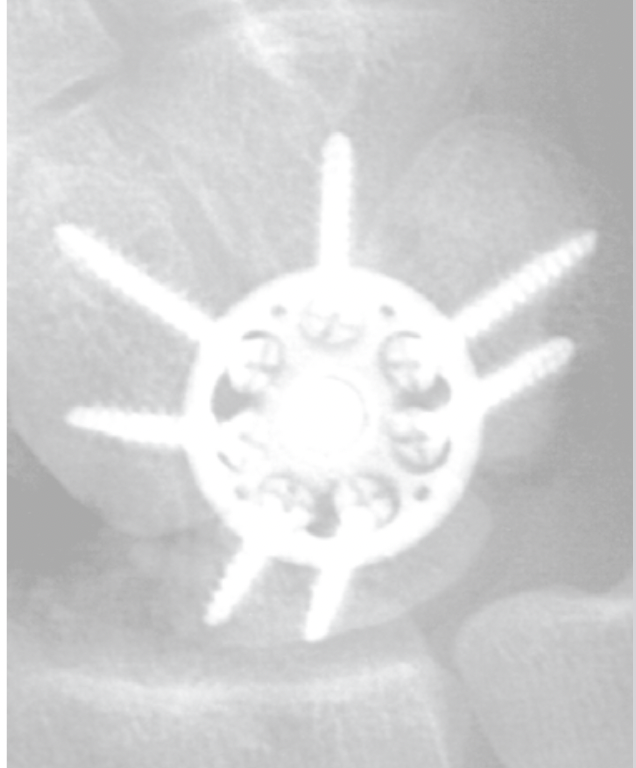

Fixation options

Dorsal locking plates

4 corner fusion techniques

Arthrex scaphoidectomy and four corner fusion with staples

Acumed four corner fusion plate surgical technique PDF